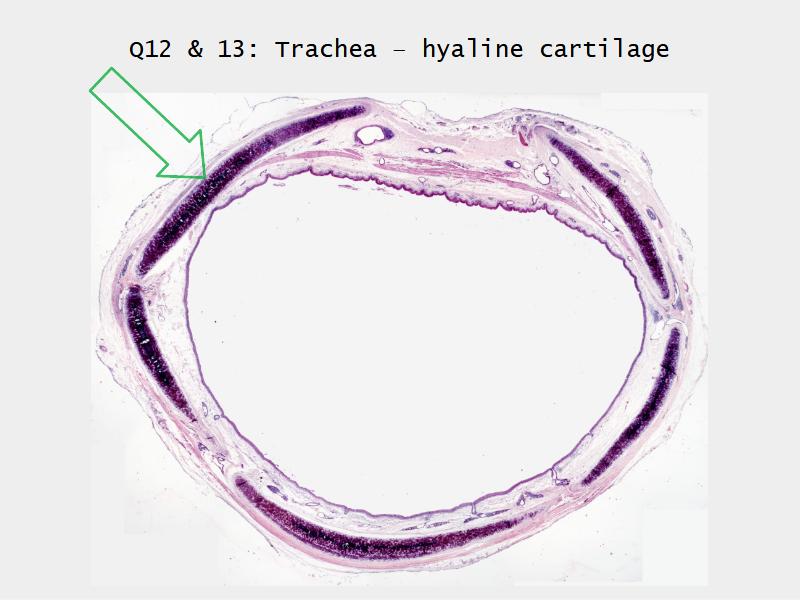

Slides: Respiratory System

- Slide 73: Trachea

Trachea